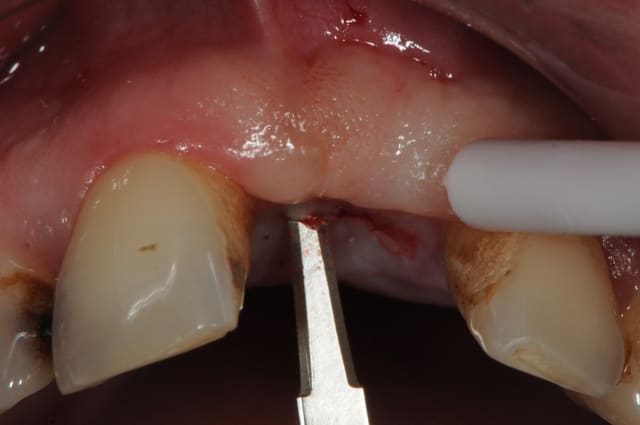

Dans le cas présenté, les images sont sur-exposées, couleur fade.

Avec un parodonte épais comme celui-ci, former la gencive n'est pas trop difficile.

With a gum biotype like this on, manipulating the gum is not very difficult.

Il y a aussi un gummy-smile et un sourire inversé, dommage après tant de couronnes.

The final result is a gummy smile with reverse smile line...too bad after all those crowns. A simple perio surgery could have give better result.